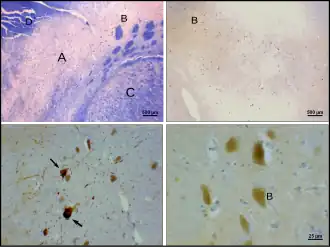

Клетки этой субстанции богаты одной из форм природного пигмента меланина — нейромеланином, который и придаёт ей характерный тёмный цвет. В чёрной субстанции различают дорсально расположенный компактный слой (pars compacta) и вентральный (pars reticulata) — сетчатый слой[6]. Pars compacta лежит медиальнее pars reticulata. Иногда упоминается и третий латеральный слой — pars lateralis, хотя его обычно классифицируют как часть pars reticulata. Pars reticulata и внутренняя часть бледного шара разделяются внутренней капсулой[7].

Чёрная субстанция играет весьма значимую роль в развитии многих заболеваний, включая болезнь Паркинсона. В чёрной субстанции расположены тела нейронов, аксоны которых, составляющие нигростриарный путь, проходят через ножки мозга, внутреннюю капсулу и оканчиваются в неостриатуме в виде широкого сплетения терминальных микровезикул с высоким содержанием дофамина. Именно этот путь является тем местом в мозге, поражение которого приводит к формированию синдрома паркинсонизма[15].

Болезнь Паркинсона является нейродегенеративным заболеванием, характеризующимся гибелью дофаминергических нейронов в pars compacta чёрной субстанции, причины, которой до сих пор неизвестны. Для болезни Паркинсона характерны двигательные нарушения: тремор, гипокинезия, мышечная ригидность, постуральная неустойчивость, а также вегетативные и психические расстройства[16] — результат снижения тормозящего влияния бледного шара (globus pallidus), расположенного в переднем отделе головного мозга, на полосатое тело (striatum). Повреждение нейронов паллидума приводит к «торможению торможения» периферических двигательных нейронов[16] (мотонейронов спинного мозга). На данный момент болезнь неизлечима, однако существующие методы консервативного и оперативного лечения позволяют значительно улучшить качество жизни больных[16]. С помощью позитронно-эмиссионной томографии доказано, что темпы дегенерации нейронов чёрной субстанции при болезни Паркинсона намного выше, чем при нормальном старении[17].